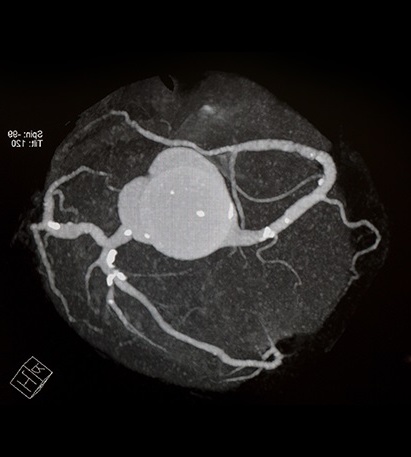

A test that can detect early signs of atherosclerosis in the coronary arteries.

CT heart calcium score, also called CT heart (computed tomography) is a quick and non-invasive X-ray examination of the coronary arteries based on computed tomography (CT). CT and CT are two names for the same type of examination. The method measures the amount of calcium (calcification) in the coronary arteries. Calcification occurs when fat, cholesterol and inflammatory processes over time contribute to plaque formation in the blood vessels, a condition called atherosclerosis or atherosclerosis.

By identifying how much calcium is present in the coronary arteries, the examination can estimate the risk of future cardiovascular disease, such as heart attack. The method is therefore often used as a complement to traditional risk assessments based on blood tests, blood pressure and lifestyle factors. Calcium score is particularly valuable because calcifications often develop long before symptoms occur. The examination can therefore identify early signs of cardiovascular disease even in people who otherwise feel healthy.

The examination measures the amount of calcium in the coronary arteries and provides a numerical value – a so-called calcium score. The higher the value, the greater the amount of calcified plaque in the vessels and the higher the risk of future cardiovascular disease.

- Score 0 – no detectable calcifications.

- Score 1–99 – small amount of calcification.

- Score 100–399 – moderate amount of calcification.

- Score 400 or higher – pronounced calcification and increased risk of coronary artery disease.

Computed tomography with calcium score can detect calcified atherosclerotic plaques in the coronary arteries. These changes occur when fat, cholesterol, calcium and inflammatory processes accumulate in the artery wall over time. By measuring the amount of calcium in the coronary arteries, the examination can show whether there are signs of atherosclerosis and provide an estimate of how widespread the calcified plaque burden is.